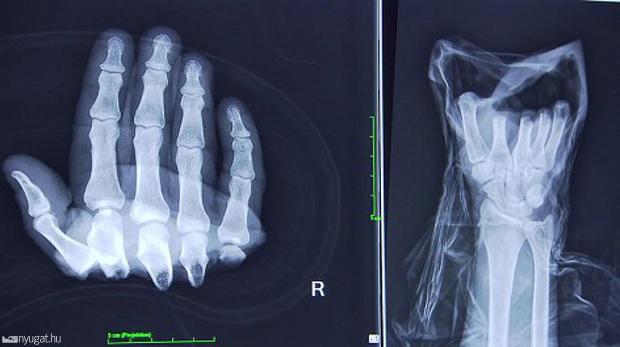

Öt ujját vágta le egy munkagép az Ausztriában dolgozó férfinek, szerencsére időben mentették meg az orvosok.

Egy magyar munkás mind az öt ujját levágta egy gép Ausztriában, a bécsi orvosoknak még időben sikerült visszavarrni azokat, a férfi azóta már mozgatni is tudja az ujjait – írta az ausztriaimunkak.hu-ra hivatkozva a Nyugat. A baleset pénteken történt Rohrbachban, a magyar dolgozó lekapcsolta a lemezmegmunkáló gépet, hogy állítson rajta,

azonban az mégis beindult és levágta mind az öt ujját.

A sérültet egy bécsi kórházba szállították, ahol Alexander Meznik kézsebész főorvos és csapata sikeresen visszavarrta az ujjakat. A nyolcórás műtét alatt először a csontokat kötötték össze, majd az inakat, idegpályákat, ereket.